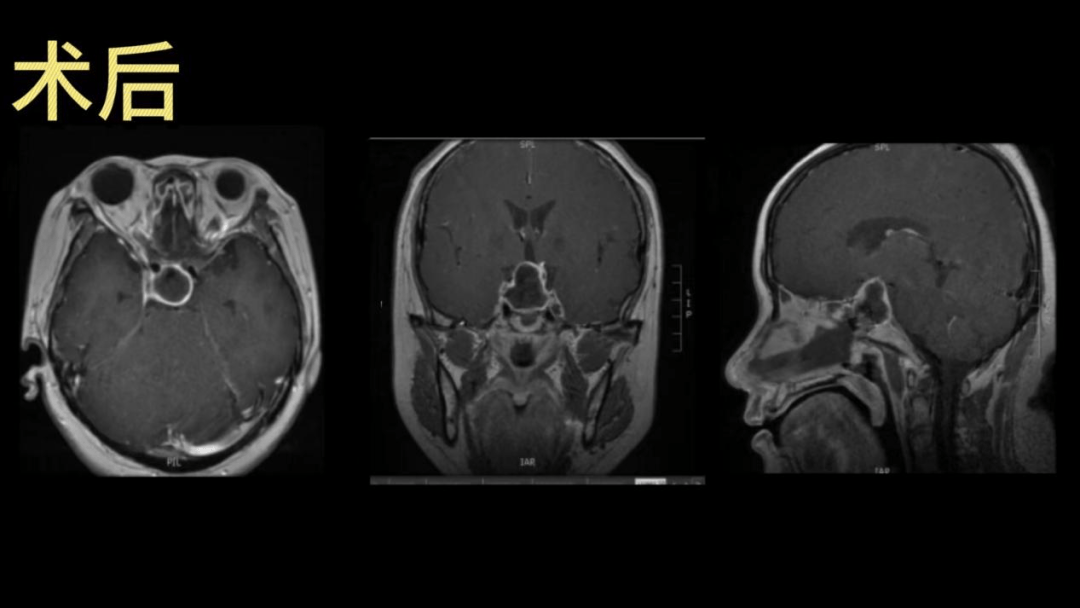

西安医学院一附院多学科联合救治一例复杂垂体瘤卒中患者